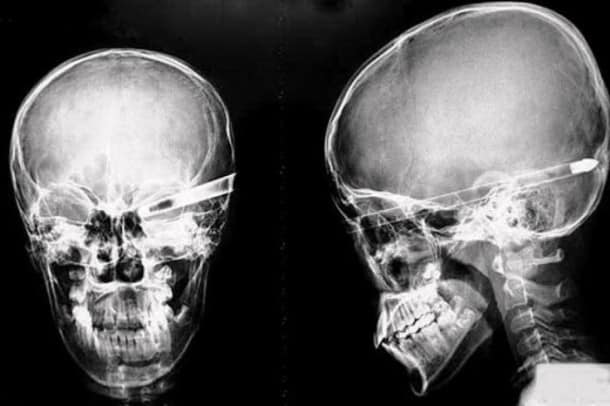

Accident, incident de pistolet à clous ou introductions douteuses de choses douteuses dans des parties douteuses de leur corps…voilà un petit aperçu de ce que voient les médecins au quotidien…

Certaines radiographies sont impressionnantes mais relèvent d’accidents…d’autres en revanche…